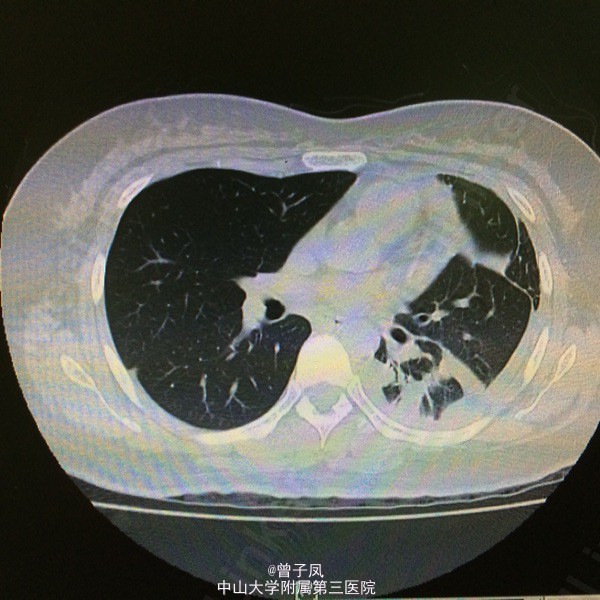

诊断:结核性渗出性胸膜炎,肺结核? 行胸腔闭式引流,引流出淡黄色液体,送胸水检查示渗出性,以淋巴细胞为主。复查胸片示胸水较前吸收后,查胸部CT示:考虑左肺浸润性肺结核并结核性胸膜炎,右下肺炎症。 予“异烟肼、利福平、乙胺丁醇”抗结核治疗,并与拜复乐抗感染治疗,辅以止咳治疗。